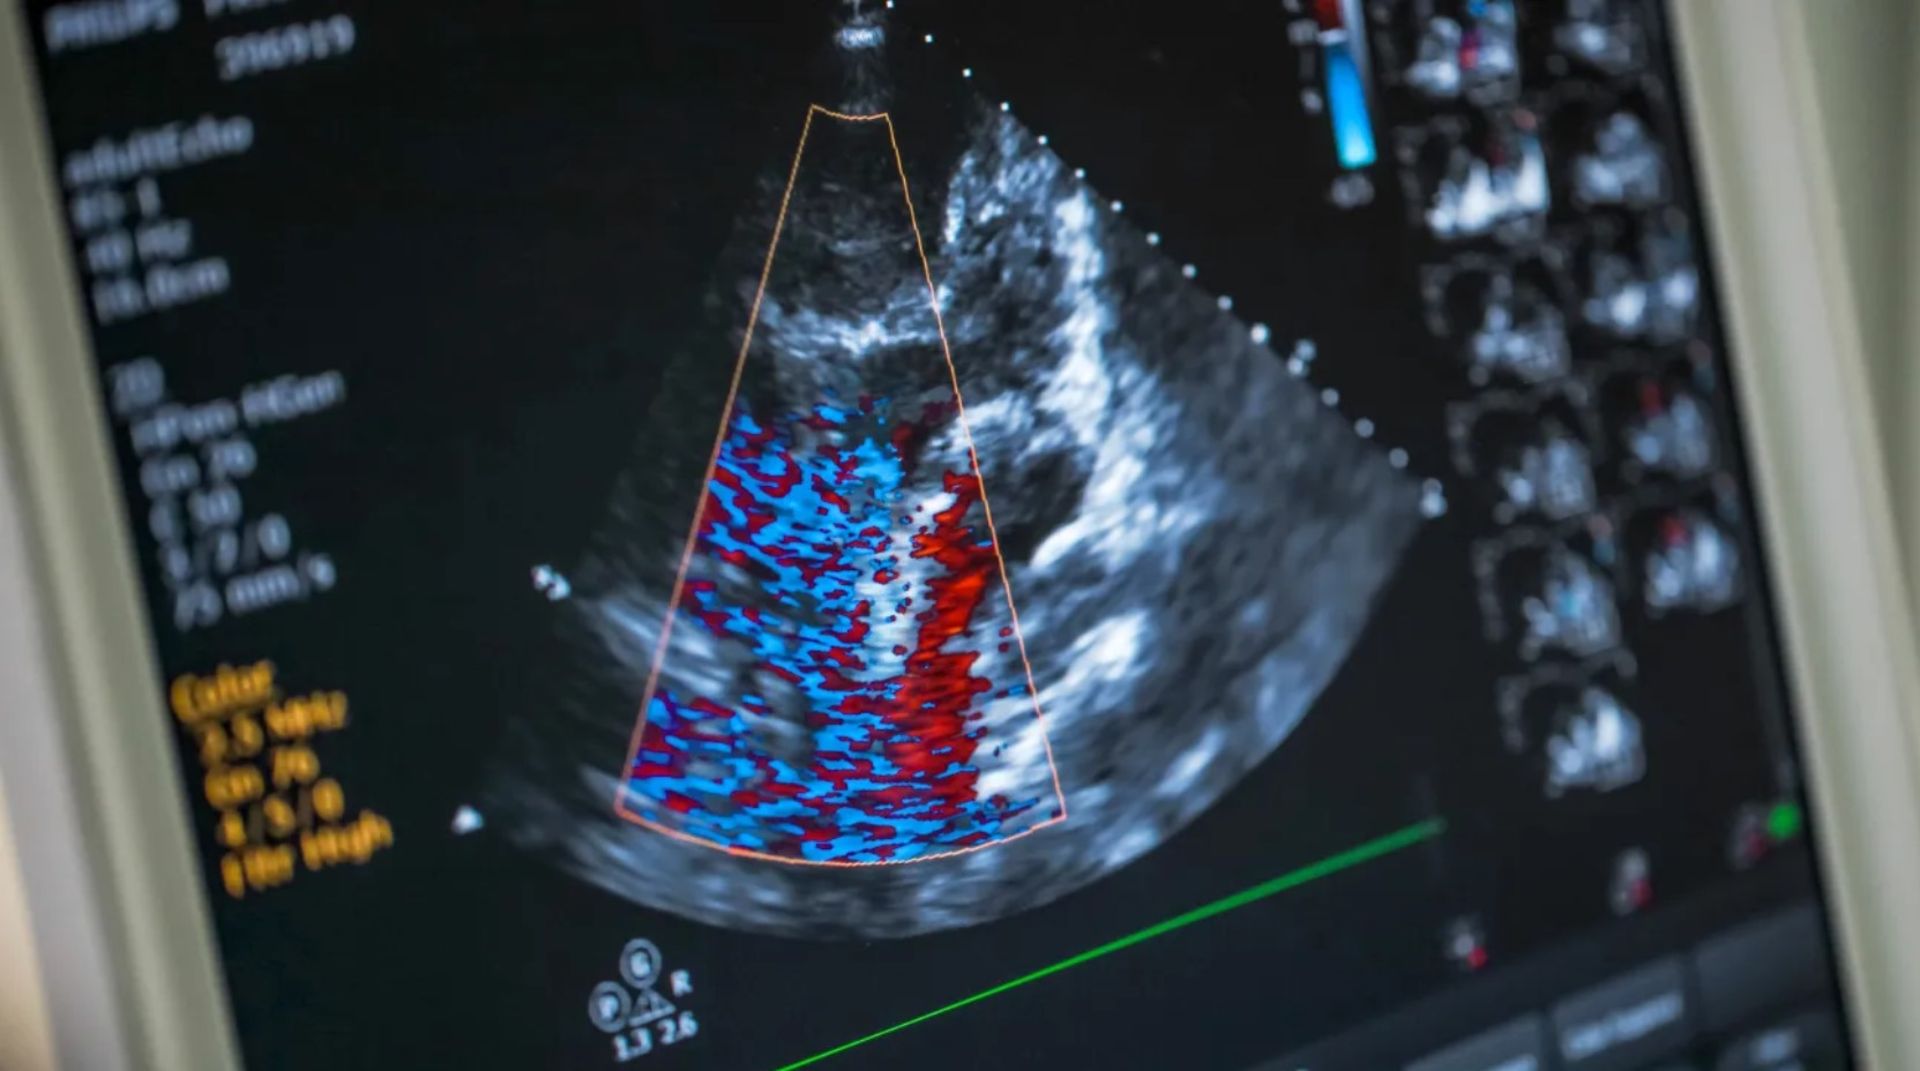

اکوکاردیوگرافی یا «اکو» آزمایشی است که در آن از امواج صوتی برای تولید تصاویر زنده از قلب انسان استفاده می‌شود. به‌تصاویر به‌دست‌آمده از این آزمایش اکوکاردیوگرام می‌گویند. آزمایش اکو و گزارش اکوکاردیوگرام به‌دست‌آمده از آن امکان بررسی دقیق عملکرد قلب و دریچه‌های آن را برای پزشکان فراهم می‌کند. تصاویر اکوکاردیوگرافی می‌توانند به پزشکان درباره‌ی جمع‌آوری اطلاعات مختلفی کمک کنند؛ ازجمله:

اکوکاردیوگرافی سه‌بعدی

اکوکاردیوگرافی سه‌بعدی از اکوکاردیوگرافی ترانس مری یا ترانس توراسیک برای ایجاد تصویر سه‌بعدی از قلب بیمار استفاده می‌کند. تصویر بالا درواقع شامل چندین تصویر از زوایای مختلف است. این نوع اکو اغلب قبل از جراحی دریچه‌ی قلب و برای تشخیص مشکلات قلبی در کودکان استفاده می‌شود. در برخی مواقع، پزشک ممکن است برای داشتن تصاویر واضح‌تر از ماده‌ی حاجب استفاده کند. در چنین حالتی، ماده‌ی حاجب به‌شکل تزریق طی اسکن وارد بدن فرد خواهد شد.